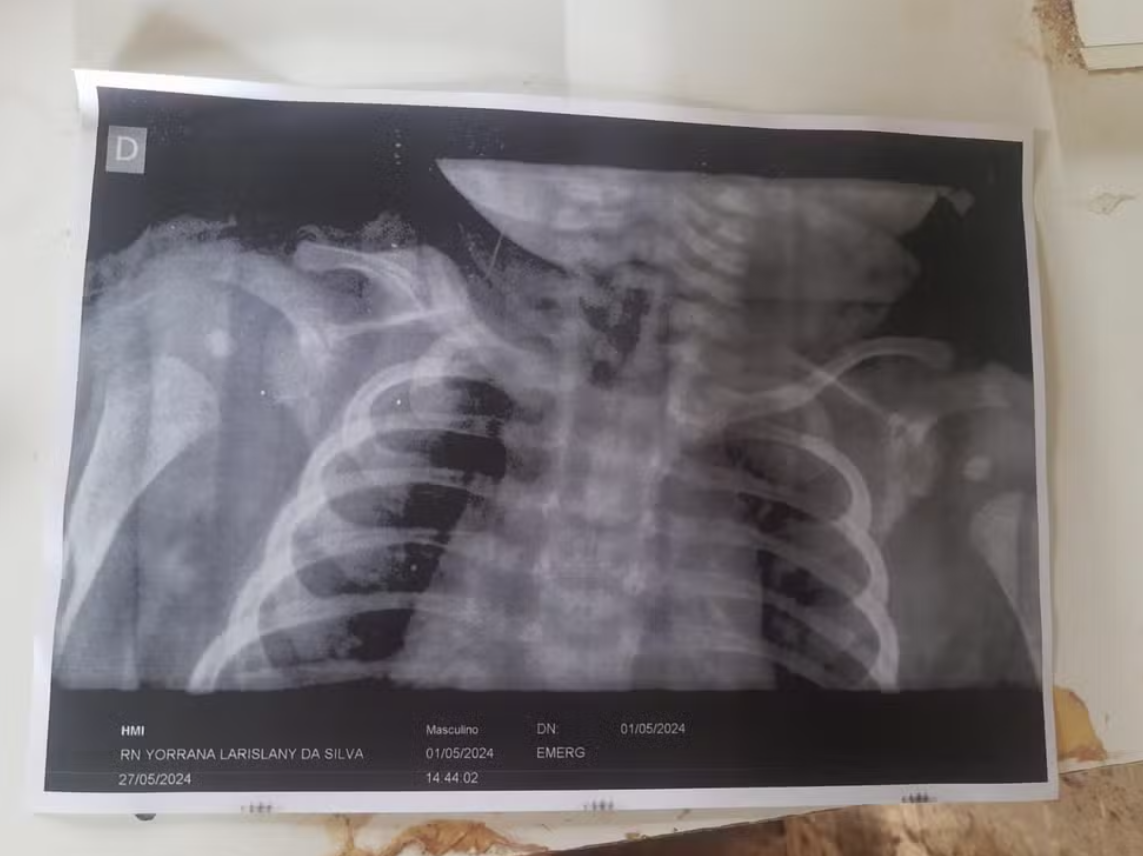

“Quando ela veio, expliquei a situação, e ela solicitou um raio-x, confirmando a fratura da clavĂcula. E mesmo os mĂ©dicos dizendo que estava tudo bem, um exame constatou que nĂŁo estava”, conta.

A jovem e o filho receberam alta no dia 5 de maio. Segundo ela, o recĂ©m-nascido continuava chorando todas as vezes que ela tocava na regiĂŁo da clavĂcula. No dia 27 de maio, ela voltou Ă maternidade e pediu uma consulta com um pediatra. Outro raio-x confirmou que a clavĂcula continuava lesionada.